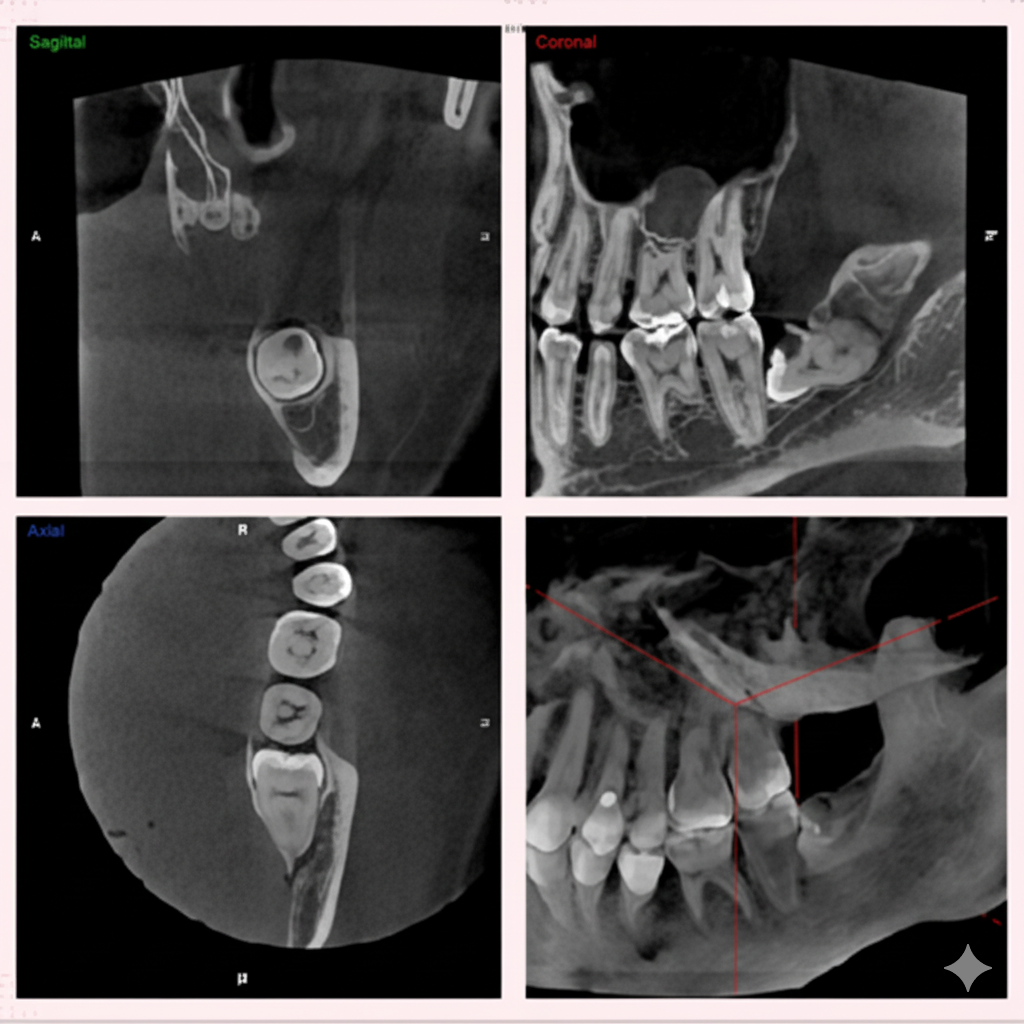

従来のレントゲン画像は平面像(二次元)でしたが、歯科用CT画像は立体画像(三次元)でみることが出来ます。

ですから、インプラントや歯周病などの診断に有効で、従来の平面画像では難しいとされた骨の幅の確認などが行えます。CT撮影で様々な角度から診断することで、正確な診査・診断に役立ち、より安全で確かな治療を行うことが可能となります。

CT画像からは、骨の形や欠損状態がわかるだけでなく、神経の位置や向きなどもしっかり把握できますので、特に、以下のような治療で役立っています。

インプラント治療では、CTの画像から埋入する部位の骨の状態(質や厚み、高さ、形態など)を正確に読み取り、そこから治療計画を立てることが出来ます。歯科用CTでの撮影画像をもとに、的確な治療計画を立てることは、安心な治療への第一歩です。また三次元の立体画像から、神経などを避けた安全な位置、方向、深さを決定し埋入する事が可能となり、より安心・安全な治療を提供する事が出来ます。

歯周病は、細菌感染による骨の破壊が起きる病気であるため、骨の破壊の程度などをよりリアルに見て判断することができます。また、骨の状態からおおよその 歯の寿命を積算することも可能です。従って、非常に予知性の高い治療が行えます。 歯科用CTを使った検診を行うことで、歯を支えている骨の状態などを直接的に見ることが出来ます。

歯の神経や根っこに潜む細菌をきれいに取り除く、根管治療。CT画像では、根の本数や神経の入っている管の方向、そして位置を正確に把握することができます。また、細かい根の破折も発見できるので、早期治療が可能になります。

歯科用CTを親知らずの抜歯に利用することで、神経までの正確な距離や、周囲の炎症の程度、病巣の有無や大きさ、位置なども判断・考慮して、治療を行うことができます。また埋伏歯などの位置なども精密に判断できるので、余分な切開や骨の切削などを避けることができます。